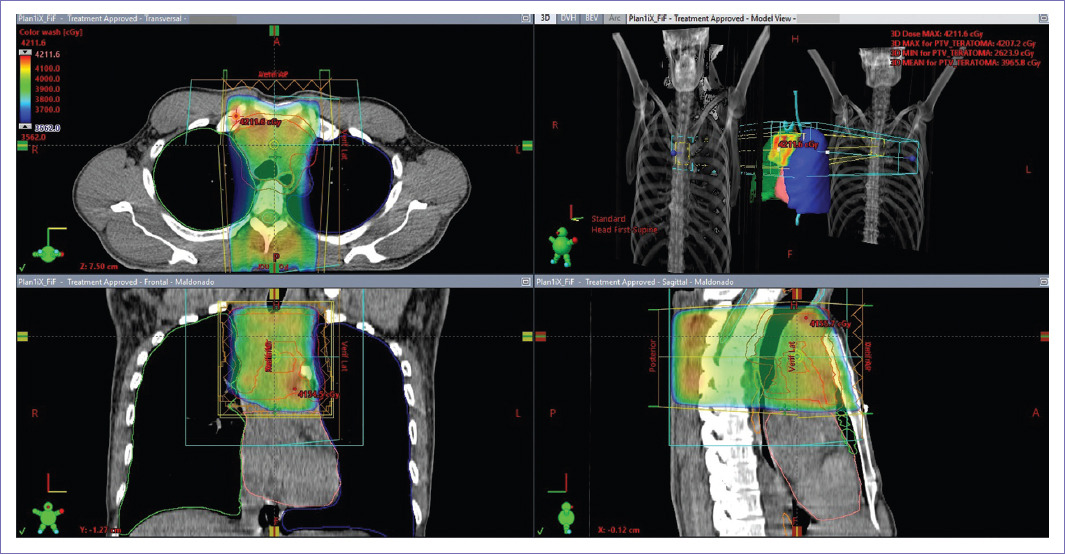

En primera valoración se encontró al paciente con taquicardia, con frecuencia cardiaca de 101 lpm, peso corporal de 76 kg e índice de masa corporal de 23. Estado funcional por Escala de Karnofsky (KPS) del 90%. Con red venosa colateral en cuello derecho. Se decidió otorgar tratamiento de radioterapia hipofraccionada con la finalidad preoperatoria vs. paliativa. Se planeó tratamiento a dosis de 37.5 Gy en 15 fracciones, para otorgar 1 fracción/día, de lunes a viernes. La técnica utilizada fue radioterapia de intensidad modulada, con delimitación de volúmenes de tratamiento de acuerdo con la comisión internacional de unidades y medidas de radiación (ICRU) en su reporte número 83 (Figs. 2 y 3)10.

Figura 3 Tomografía computarizada simple de planeación de tratamiento de octubre 2021. Representación gráfica de la distribución volumétrica de la dosis prescrita.